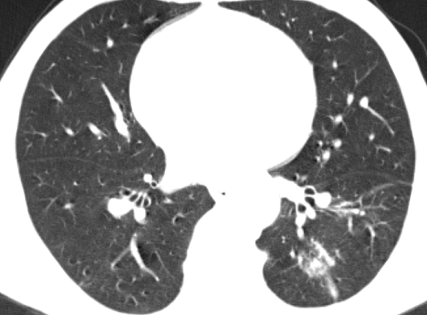

经过精心治疗,王某的症状完全消失。一个月后复查胸部 CT,结果显示较前明显吸收,这标志着王某的病情得到了有效控制,向着康复迈出了坚实的一步。信丰县中医院肺病科专家团队以卓越的医疗水平和高度的责任心,再次为患者带来了健康和希望,也赢得了广大患者的信任和赞誉。

治疗后CT影像▲